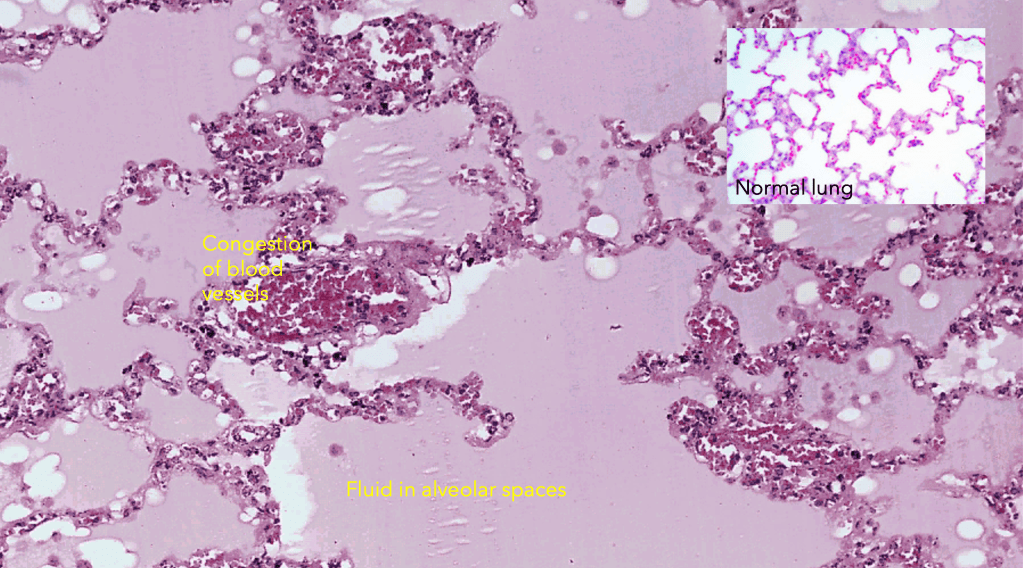

Pulmonary oedema is a condition in which fluid accumulates within the normally air-filled alveolar space resulting in impaired pulmonary gas exchange. This usually results from increased hydrostatic pressure in the pulmonary venous circuit.

The most common cause associated with pulmonary oedema is left ventricular failure (LVF). In LVF, there is reduced ejection fraction with increased end-diastolic volume and cardiac pre-load. The pooling of blood and increased pre-load causes an increase in left atrial pressure and pulmonary venous pressure, and consequently increased pulmonary capillary hydrostatic pressure. The increase hydrostatic pressure causes increased nett filtration of water out of the capillaries into the pulmonary alveolar space.

Pulmonary congestion

Congestion in the lungs is a feature often seen in association with pulmonary oedema. This is because pulmonary oedema most commonly results from left ventricular failure or left valvular disease that obstructs the outflow of blood from the lungs through the pulmonary vein and the left cardiac chambers

In addition to the engorged dilated pulmonary blood vessels due to congestion, and fluid filled alveolar spaces associated with pulmonary oedema one may also appreciate the presence of haemosiderin laden macrophages in chronic pulmonary congestion.